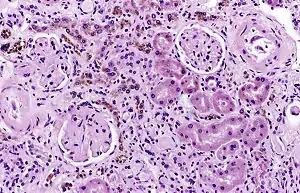

| Image of a kidney viewed under a microscope. The brown areas contain hemosiderin | |

Hemosiderin deposition in the lungs is often seen after diffuse alveolar hemorrhage, which occurs in diseases such as Goodpasture's syndrome, granulomatosis with polyangiitis, and idiopathic pulmonary hemosiderosis. Mitral stenosis can also lead to pulmonary hemosiderosis. Hemosiderin collects throughout the body in hemochromatosis. Hemosiderin deposition in the liver is a common feature of hemochromatosis and is the cause of liver failure in the disease. Selective iron deposition in the beta cells of pancreatic islets leads to diabetes[4][2] due to distribution of transferrin receptor on the beta cells of islets[3] and in the skin leads to hyperpigmentation. Hemosiderin deposition in the brain is seen after bleeds from any source, including chronic subdural hemorrhage, cerebral arteriovenous malformations, cavernous hemangiomata. Hemosiderin collects in the skin and is slowly removed after bruising; hemosiderin may remain in some conditions such as stasis dermatitis. Hemosiderin in the kidneys has been associated with marked hemolysis and a rare blood disorder called paroxysmal nocturnal hemoglobinuria.